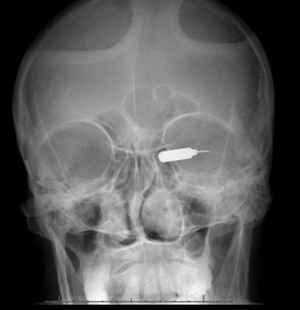

X-rays and a CT scan confirmed the location of the TASER dart’s fish hook barb in the orbital implant.

Figure 5. X-ray showing the TASER dart in the left orbit.